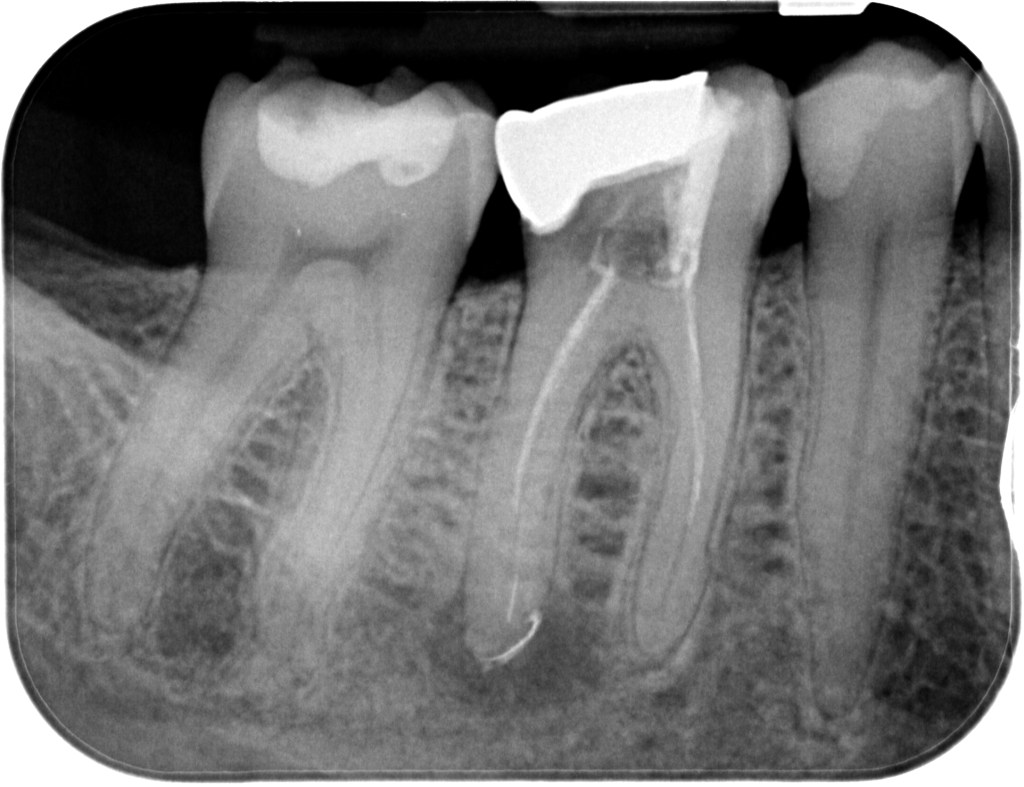

18.11.2022 Patientin DW, geb. am 12.04.1968, Zahn 46,26, WF Revision, WF-Kontrolle im Recall